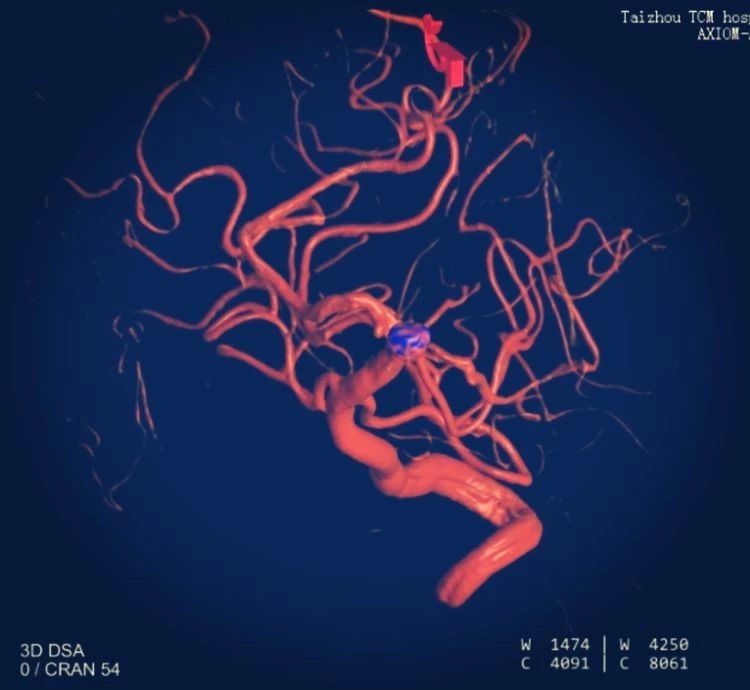

術(shù)中影像重建顯示的不同角度的動脈瘤,看起來很漂亮哦